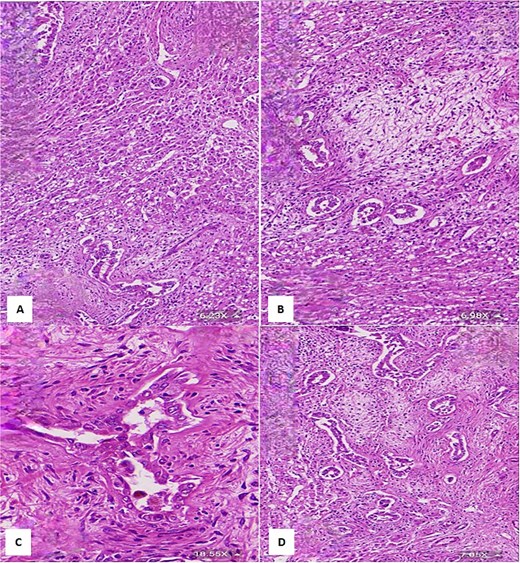

Final histopathological examination of the resected 17 cm mass confirmed the diagnosis of HMH (Figs 4 and 5). The patient recovered well postoperatively.

(A) Histological section showing interspersed islands of hepatocytes with retention of normal cell plate architecture (hematoxylin & eosin, 6.23×). (B) Myxoid area with benign duct structures and interspersed normal hepatocytes (hematoxylin & eosin, 6.98×). (C & D) Dilated and branching bile ducts show no cytological atypia (hematoxylin & eosin: C- 18.55×, D- 7.05×).

(A & B) Vimentin immunostain demonstrating positive cytoplasmic staining in neoplastic cells (6.26×). (C) CK7 immunostain highlights the benign bile duct epithelium (3.64×). (D) GLUT1 immunostain shows negative staining in neoplastic cells and positive staining in red blood cells (internal control) (11.44×).